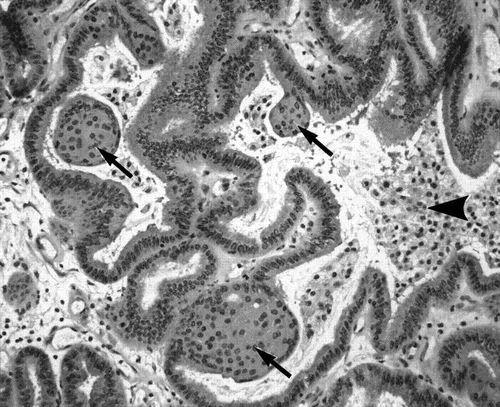

箭头示意为进入脑内的子宫内膜组织。来源:https://www.ajronline.org/doi/full/10.2214/ajr.182.6.1821543

目前,科学文献中有明确病理学诊断的脑子宫内膜异位症(cerebral endometriosis)仅有 4 例,还有 2 例通过影像学手段在脑内确定了病灶位置,但缺乏组织学证据。在这些案例中,离经叛道的子宫内膜细胞侵入了患者的脑干、小脑、大脑额叶和顶叶皮层,甚至深入了连接两个半球的胼胝体白质。这些周期性增生和脱落的团块压迫了患者的脑组织,几乎令每个人都出现了经期性癫痫和运动或感觉异常。

箭头处为脑内被怀疑为子宫内膜异位的病灶。来源:https://www.ajronline.org/doi/full/10.2214/ajr.182.6.1821543